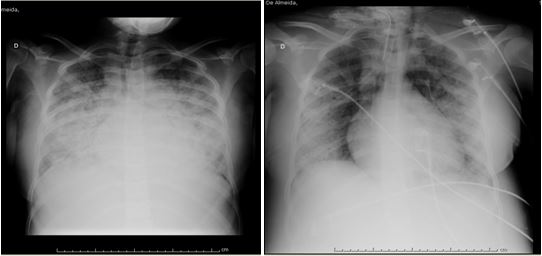

Paciente evoluiu com quadro de insuficiência respiratória aguda admitida no CTI apresentando como diagnósticos: varicela disseminada, pneumonia grave, SARA e sepse grave, estava consciente, pouco sonolenta, taquidispnéica, com esforço respiratório importante em uso de musculatura acessória, com bulhas normorrítmicas e normofonéticas e murmúrio vesicular fisiológico com crepitações em bases pulmonares, radiografia de tórax evidenciando padrão de SARA (Síndrome da angústia respiratória no adulto). Resultado de exames: hemoglobina: 10,22g/dl, hematócrito: 31%, plaquetas: 196.000/mm³, segmentados: 16%, PTTA: 87 segundos, potássio: 3.1 mEq/l, sódio: 132 mEq/l, global de leucócitos: 15.900, gasometria: PH: 7.11, PCO2: 80, PO2: 75, Na: 133, K+: 3.1, Ca++: 1.15, Lactato: 2.9, HCO3: 25.4, HTC: 24, TCO: 27.9,THBC: 7.4, BEECF: 7.4.

Evolução radiográfica da paciente no CTI

O padrão radiológico mais freqüente é um infiltrado intersticial bilateral com nódulos de 2 a 10 mm. Predominantemente em bases e região peri-hilar, essas lesões podem levar meses para desaparecer e ainda cursar com calcificação residual, sendo controversa sua evolução para pneumonia intersticial usual. Derrame pleural e adenopatias mediastinais apresentam baixa freqüência (MORENO et al, 2007).